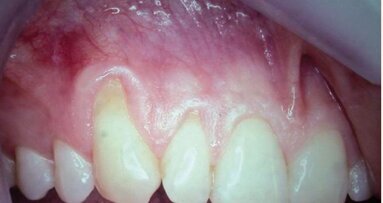

Fig. 2

C’est sa structure et composition spécifique qui va permettre la non-compétition cellulaire et par la même la constitution de l’os sous la membrane. Les cellules épithéliales vont, quant à elles, se développer en tapissant la surface lisse de cette membrane (Figs. 2 et 3).

On pourra remarquer que la membrane a été volontairement laissée exposée, afin de ne pas lever de lambeau vestibulaire ou lingual. Grâce à ceci, nous avons pu conserver la totalité de cette muqueuse attachée, ce qui nous permettra d’obtenir un résultat esthétique bien meilleur lors de la reconstruction prothétique, qu’elle soit traditionnelle (bridge ou prothèse amovible) ou sur implants, en permettant d’avoir un profil d’émergence le plus proche possible du naturel (Figs. 4–8).